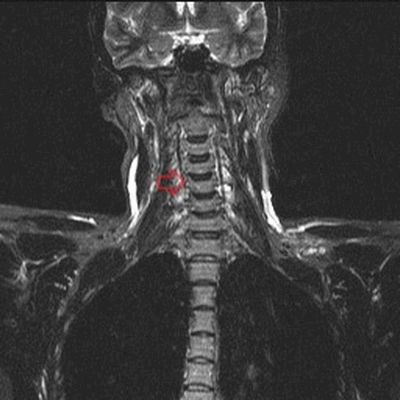

Грудной отдел позвоночника на МРТ в коронарной проекции